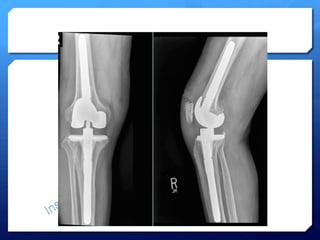

Gonarthrose

tri-­‐compartimentale

• 8.

• 9.